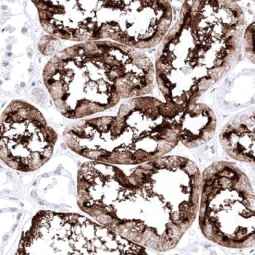

With this in mind, GeneTex is proud to introduce its HistoMAX product line that consists of antibodies specifically vetted for IHC. All of these reagents were extensively evaluated for IHC utilizing formalin-fixed normal and cancer tissue microarrays to guarantee specificity and best-in-class performance. Only antibodies that have passed these stringent performance criteria for IHC will be added to the HistoMAX portfolio.![]()